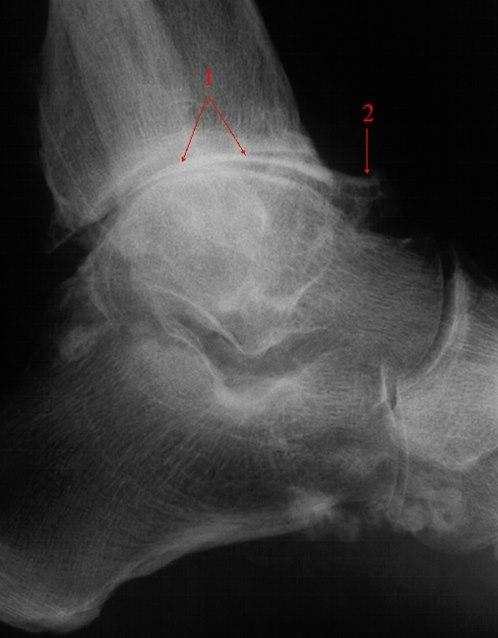

Ankelartrose, skrå frontSkade eller sykdom i leddet disponerer for utvikling av artrose. Dette kan for eksempel være ankelbrudd eller kraftig overtråkk som ikke er tilstrekkelig tilhelet. Overvekt gir også større slitasje, og disponerer for artrose. Ellers vil arbeid eller aktivitet som innebærer ekstra belastninger på bena gjennom et langt liv øke risikoen for slitasje/artrose.

Forkalkninger og redusert leddspalte.Plagene er typiske. Kombinert med vanlig legeundersøkelse av ankelen kan diagnosen være sannsynlig uten andre undersøkelser. Sikker diagnose fås ved røntgenundersøkelse som viser nedslitt brusk og eventuelt forandringer i selve beinstrukturen.